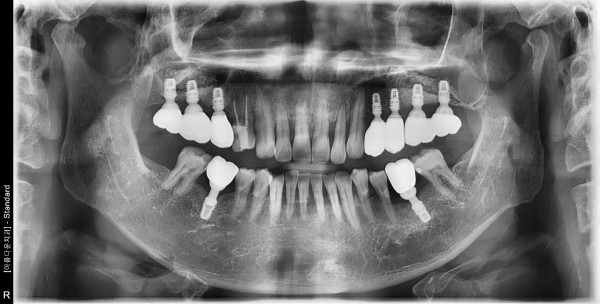

50대 남성 임플란트 식립